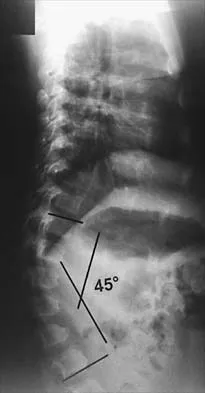

A 12-year-old girl has had lower back pain for the past 6 months that interferes with her ability to participate in sports. She denies any history of radicular symptoms, sensory changes, or bowel or bladder dysfunction. Examination reveals a shuffling gait, restriction of forward bending, and tight hamstrings. Radiographs show a grade III spondylolisthesis of L5 on S1, with a slip angle of 20 degrees. Management should consist of

Indications for surgical treatment of spondylolisthesis include pain and/or progression of deformity. Specifically, surgery is necessary when there is persistent pain or a neurologic deficit that fails to respond to nonsurgical therapy, there is significant slip progression, or the slip is greater than 50%. For patients with mild spondylolisthesis, in situ posterolateral L5-S1 fusion is adequate. In patients with more severe slips (greater than 50%), extension of the fusion to L4 offers better mechanical advantage. Postoperative immobilization may be achieved with instrumentation, casting, or both. In patients with a slip angle of greater than 45 degrees, reduction of the lumbosacral kyphosis with instrumentation or casting is desirable to prevent slip progression. Laminectomy alone is contraindicated in a child. Nerve root decompression is indicated if radiculopathy is present clinically. Seitsalo S, Osterman K, Hyvarinen H, Tallroth K, Schlenzka D, Poussa M: Progression of spondylolisthesis in children and adolescents: A long-term follow-up of 272 patients. Spine 1991;16:417-421.